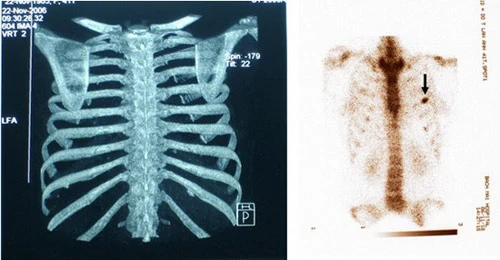

Để tiến hành phẫu thuật cắt bỏ xương sườn các chuyên gia thẩm mỹ cao tay sẽ thực hiện biện pháp can thiệp vào cấu trúc khung xương.

Các bác sĩ sẽ tiến hành rút bỏ xương sườn thứ 11 và 12.

Các chuyên gia cũng có thể rút bỏ xương sườn số 10 theo yêu cầu của bệnh nhân để tạo 1 khoảng trống nhằm định hình vòng 2 siêu nhỏ.

Loại bỏ xương sườn là một ca phẫu thuật khó. Thông thường người bệnh sẽ bị gây mê hoàn toàn trước khi tiến hành cắt bỏ và rút xương sườn.